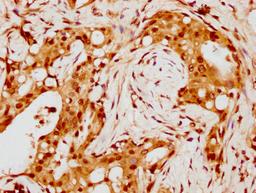

IHC image of CSB-PA010429PA88nohHU diluted at 1:8 and staining in paraffin-embedded human breast cancer performed on a Leica BondTM system. After dewaxing and hydration, antigen retrieval was mediated by high pressure in a citrate buffer (pH 6.0). Section was blocked with 10% normal goat serum 30min at RT. Then primary antibody (1% BSA) was incubated at 4°C overnight. The primary is detected by a biotinylated secondary antibody and visualized using an HRP conjugated SP system.